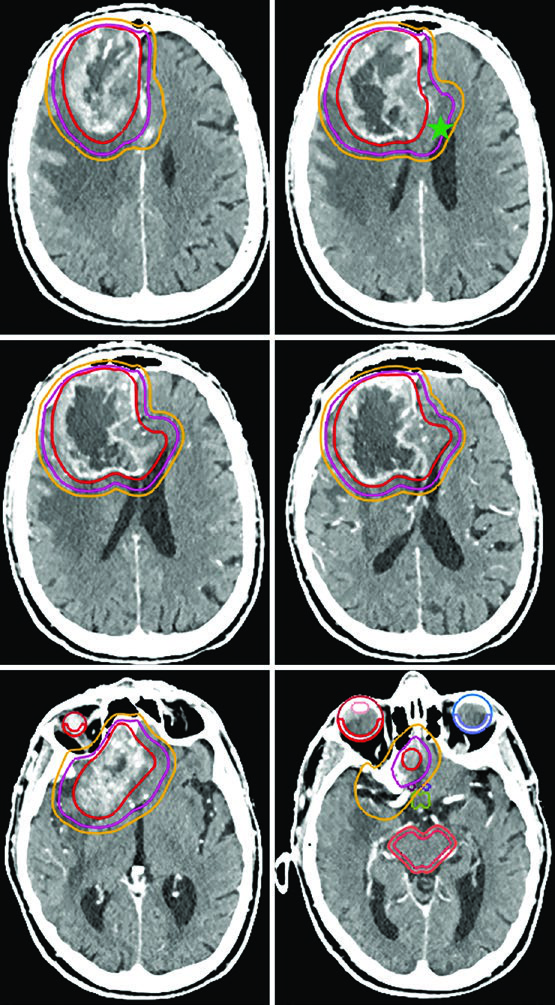

Meningioma Atípico e Maligno: Graus II e III da OMS

Para meningioma grau II, a radioterapia adjuvante pode ser considerada após ressecção macroscópica total e é recomendada após ressecção subtotal. Para grau III, a radioterapia é recomendada para todos os pacientes independentemente da extensão da ressecção. Para conhecer o manejo dos tumores benignos do SNC, confira nosso artigo dedicado sobre tumores benignos do SNC.

Um detalhe crítico que diferencia os meningiomas de grau II e III: como esses tumores podem invadir osso e parênquima cerebral, crânio e encéfalo normal não funcionam necessariamente como barreiras naturais à disseminação. Se os achados operatórios ou anatomopatológicos indicam invasão cerebral, as margens devem incluir o parênquima em risco. E para tumores recorrentes de grau II, é essencial avaliar a inserção dural original no diagnóstico inicial — ela pode ter sido sede de doença microscópica.

| Meningioma grau II (upfront) | 54–59,4 Gy (1,8 Gy/fx) | Cavidade pós-operatória, tumor residual incluindo envolvimento dural/ósseo suspeito na T1 pós-contraste | 0,5 cm restrito anatomicamente | 0,3–0,5 cm |

| Meningioma grau II (recorrente) | 54–59,4 Gy (1,8 Gy/fx) | Idem + avaliação da inserção dural prévia no diagnóstico inicial | 0,5–1,0 cm restrito | 0,3–0,5 cm |

| Meningioma grau III (upfront ou recorrente) | 59,4–60 Gy (1,8–2 Gy/fx) | Idem + inserção dural prévia | 1,0–1,5 cm restrito | 0,3–0,5 cm |

| Hemangiopericitoma | 59,4–60 Gy (1,8–2 Gy/fx) | Cavidade pós-op, tumor residual, envolvimento dural/ósseo na T1 pós-contraste | 1,5 cm restrito, mas incluir totalidade do osso envolvido | 0,3–0,5 cm |

O hemangiopericitoma merece menção especial. A expansão de CTV de 1,5 cm segue o padrão, mas diferentemente dos meningiomas, todo o osso envolvido deve ser incluído no volume sem redução em barreiras ósseas — a natureza infiltrativa desse tumor justifica essa conduta mais agressiva.